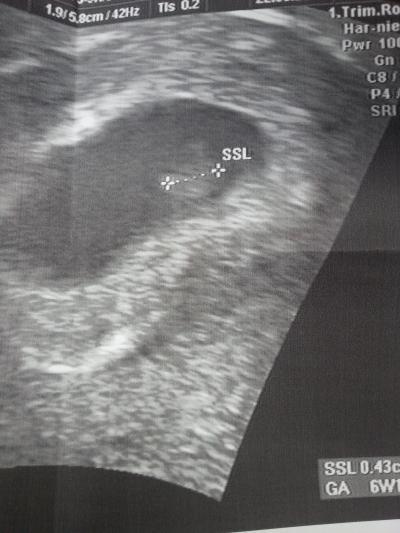

Heute war wieder FA-Termin und ich war eig voller Freude. Rechnerisch, da ich ja eine ICSI hatte bin ich eig 6+5ssw doch heute hat er mich auch 6+1 zurückgestuft. Das Baby ist 0,45 cm groß. Ich verstehe nicht wieso er mich zurückstufte. Habe gefragt aber keine Antwort bekommen. Mein nächster Termin ist erst in 4 Wochen. Wie groß waren eure Babys? Ausserdem hat es eine noch sehr gekrümmte Form ist das Normal?

Bild zu FA-Termin - Kinderwunschbehandlung